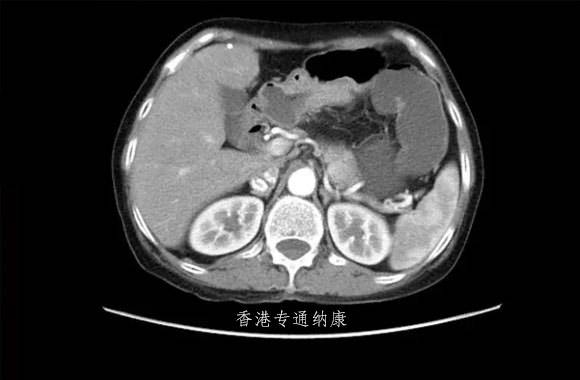

2021年1月,FDA批准阿斯利康/第一三共联合开发的DS8201扩展适用范围,用于经曲妥珠单抗治疗的HER2阳性局部晚期或转移性胃癌和胃食管结合部(GEJ)腺癌患者。获批是基于开放、随机、II期DESTINY-Gastric01研究,评估了DS-8201对HER2阳性晚期胃癌患者的疗效。纳入接受过至少两次治疗的HER2阳性胃或胃食管交界处腺癌患者,所有患者随机分组,分别接受DS-8201(6.4mg/kg,q3w)或化疗。